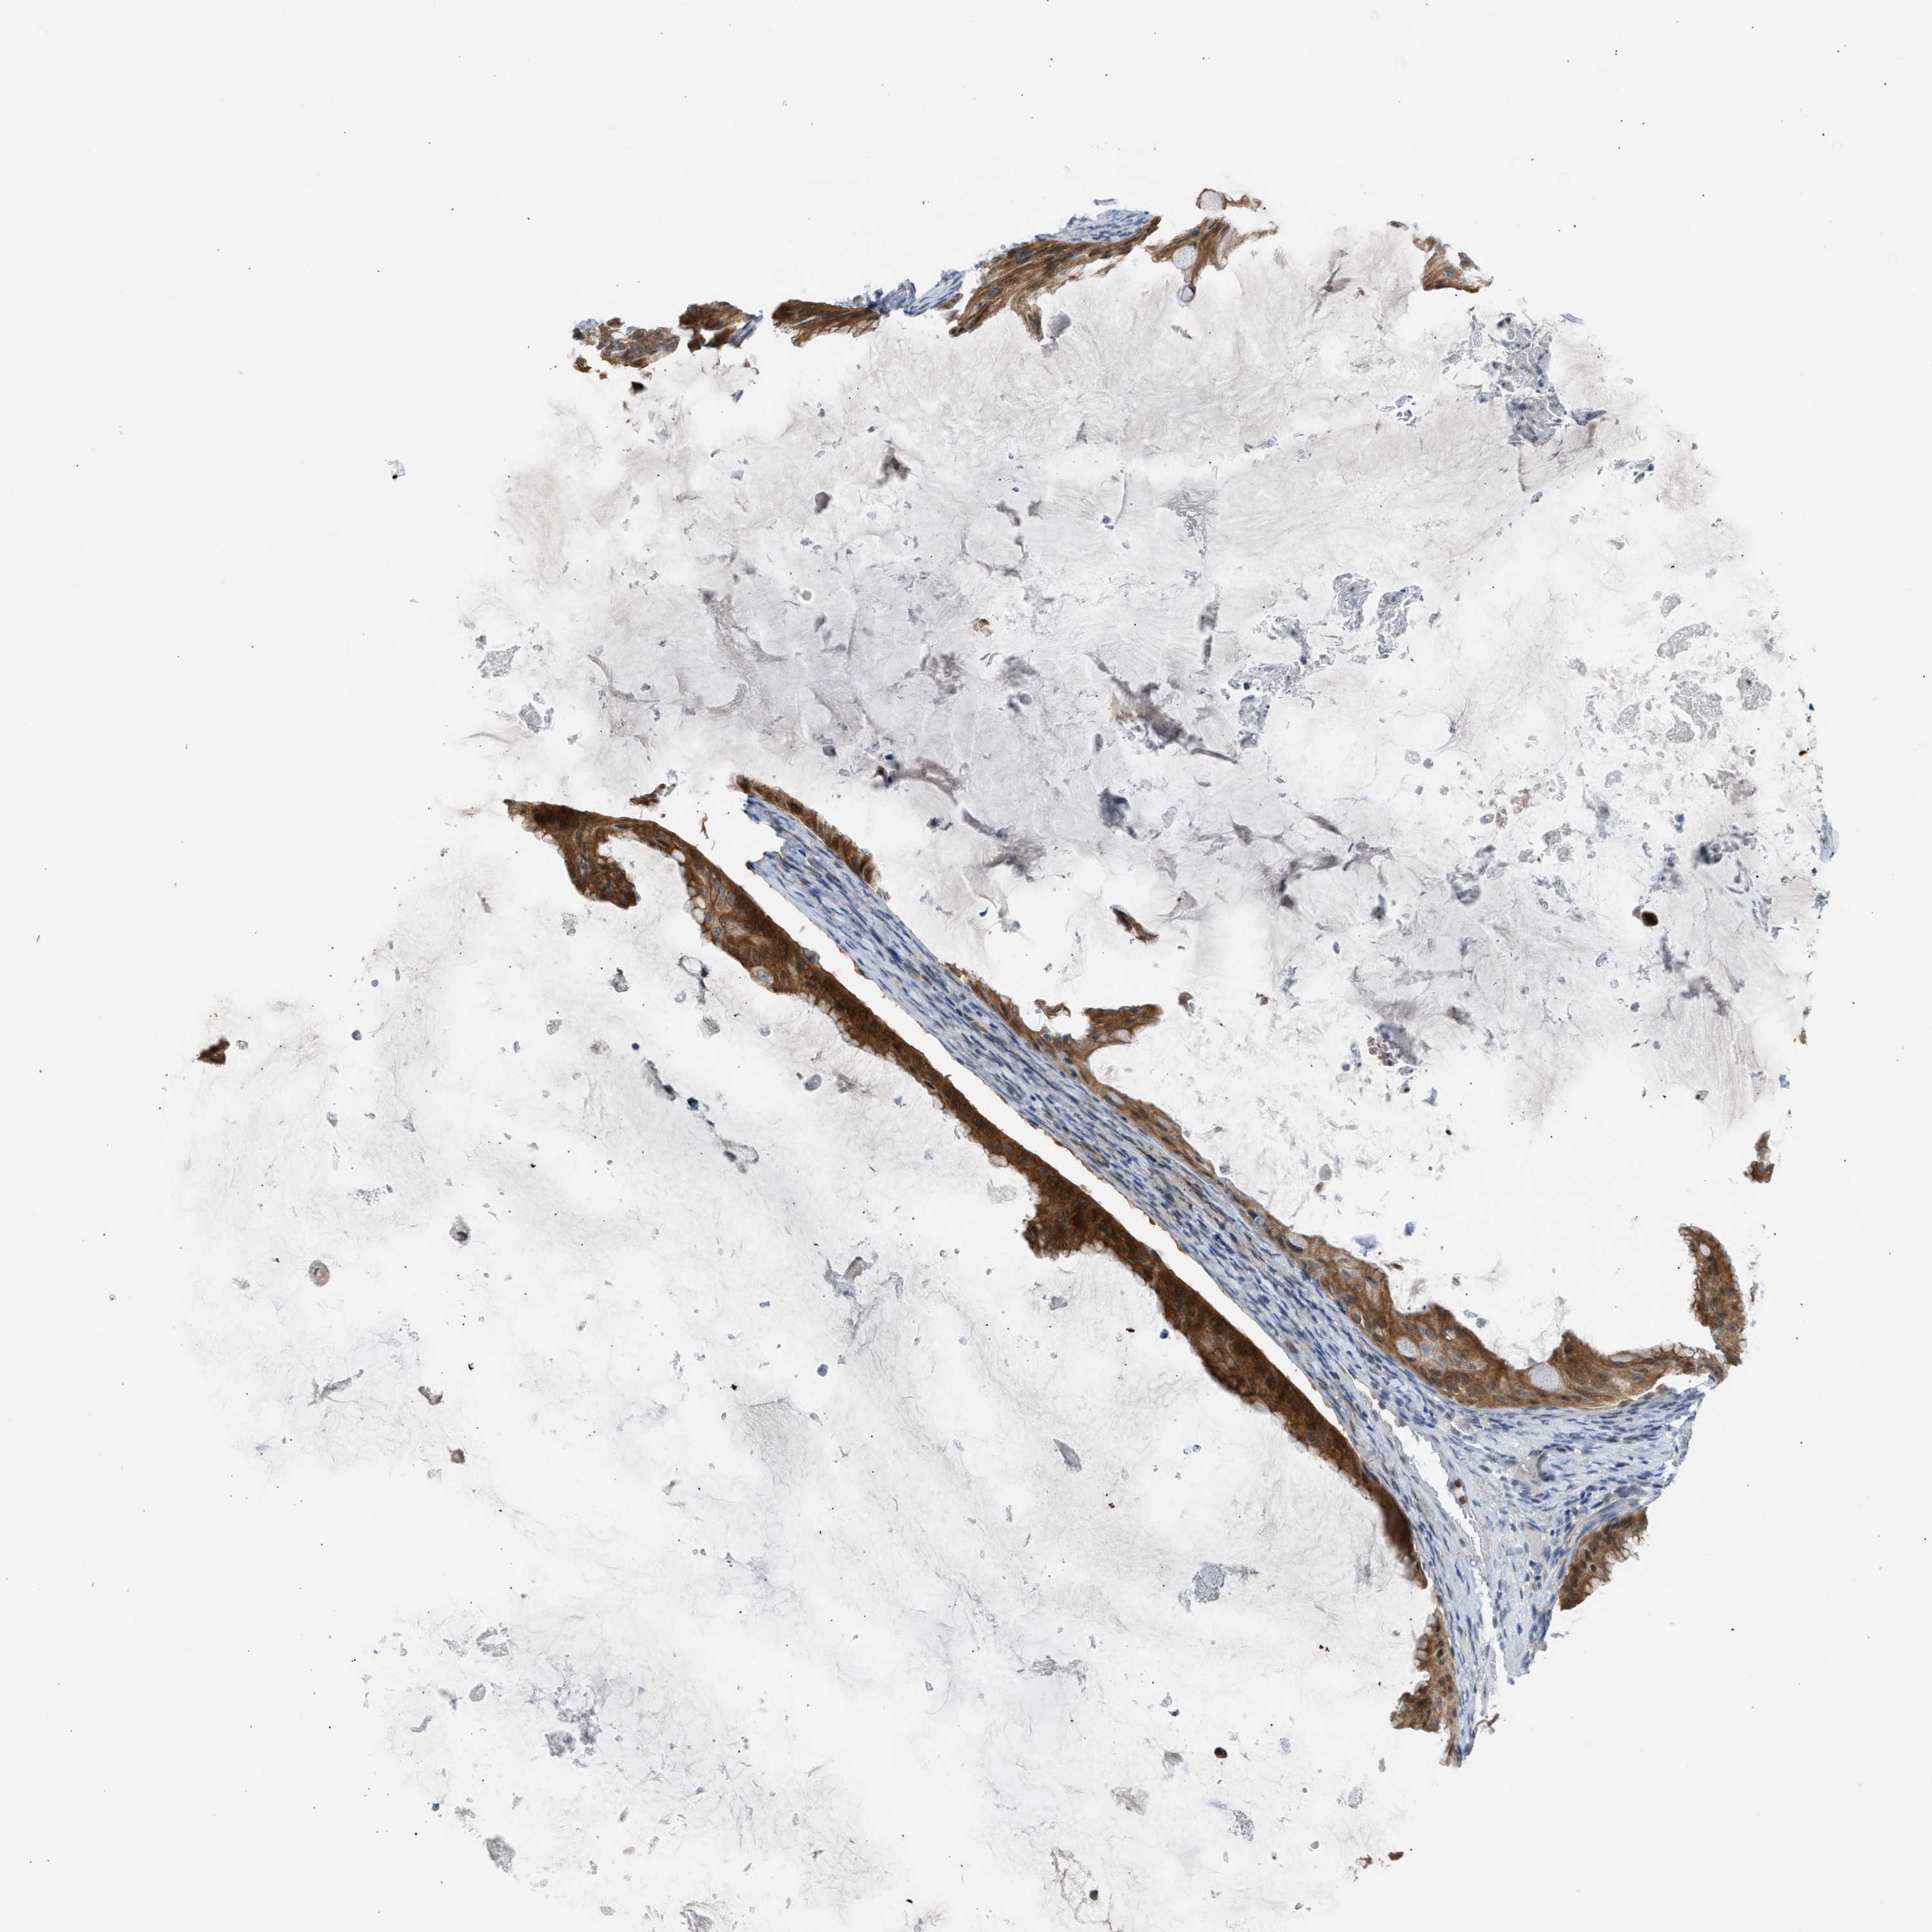

OVARIAN CANCER - Protein expressioni

A mouse-over function shows sample information and annotation data. Click on an image to view it in a full screen mode. Samples can be filtered based on level of antibody staining by selecting one or several of the following categories: high, medium, low and not detected. The assay and annotation is described here.

Note that samples used for immunohistochemistry by the Human Protein Atlas do not correspond to samples in the TCGA dataset.

Antibody stainingi

Antibody staining in the annotated cell types in the current human tissue is reported as not detected, low, medium, or high, based on conventional immunohistochemistry profiling in selected tissues. This score is based on the combination of the staining intensity and fraction of stained cells.

Each image is clickable and will lead to virtual microscopy that enables deeper exploration of all samples and also displays staining intensity scores, fraction scores and subcellular localization as well as patient and tissue information for each sample.

Antibody CAB020139

Staining

High

Medium

Low

Not detected

Intensity

Strong

Moderate

Weak

Negative

Quantity

>75%

75%-25%

<25%

None

Location

Nuclear

Cytoplasmic/membranous

Cytoplasmic/membranous,nuclear

Cystadenocarcinoma, serous, NOS

Carcinoma, endometroid

Cystadenocarcinoma, mucinous, NOS

Carcinoma, NOS